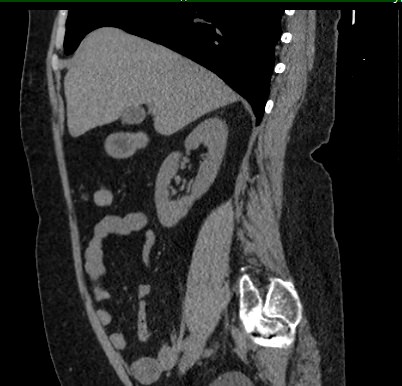

Мультиспиральная компьютерная томография (МСКТ) брюшной полости относится к современным лучевым методам исследования, с помощью которого можно оценить состояние органов брюшной полости (печени, желчного пузыря, поджелудочной железы, селезенки), прилегающих к ним кровеносных сосудов и лимфатических узлов.

С помощью мультиспиральной компьютерной томографии проводятся послойные рентгеновские снимки исследуемой области с толщиной среза от 0,5 мм. В нашей клинике исследование выполняется на компьютерном томографе экспертного класса TOSHIBA AQUILION CXL, который оснащен 128 детекторами, позволяющими получать за несколько секунд снимки брюшной полости с высокой точностью. Большое количество детекторов позволяет получить точные данные, при этом сократить время исследования и сделать минимальной лучевую нагрузку на пациента. Кроме того, инновационные технологии аппарата дают возможность сформировать объемную модель органа и окружающих структур, что также способствует проведению точной и достоверной диагностики.

При подозрении на опухоли, воспалительные процессы, гнойные очаги назначается КТ брюшной полости с внутривенным болюсным контрастированием. Для этого пациенту внутривенно вводится рентгеноконтрастное вещество на основе йода. Благодаря усиленному кровоснабжению препарат накапливается в структуре патологических образований и помогает врачу-рентгенологу выявить изменения в структуре внутренних органов.

Метод контрастирования помогает максимально точно выявить очаг патологии уже на начальной стадии, а также установить его локализацию, точные размеры, форму и особенности кровоснабжения.